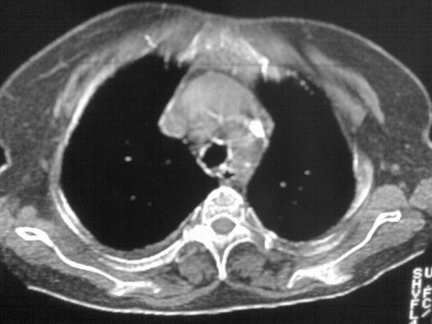

标题: CT13142:女 80 胸闷、气短、1w [打印本页]

标题: CT13142:女 80 胸闷、气短、1w

右肺炎性变,双侧甲状腺肿,胸膜肥厚。

右肺炎性变

双侧胸腔积液

缩窄性心包炎

左室为主的心脏增大。

右肺感染;双侧胸腔少量积液,心影增大,可能与心功不全有关;胸内甲状腺肿。

右肺炎性变,双侧甲状腺肿,胸膜肥厚,心影增大考虑心功能不全.

胸内甲状腺肿;右肺感染;双侧胸腔少量积液。

胸内甲状腺肿;右肺中叶感染;双侧胸腔少量积液;心影增大,考虑有心功能不全。